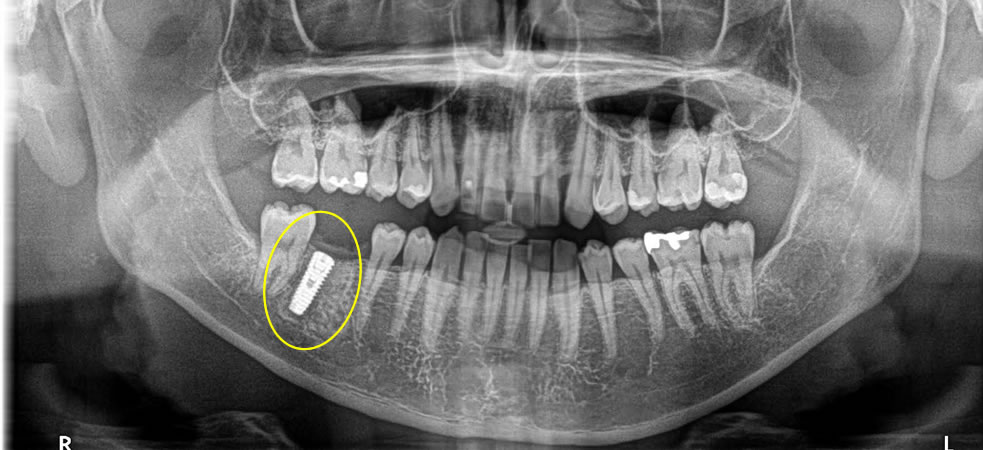

インプラント治療完了後のレントゲン・口腔内写真

その後、2週間で抜糸をし、5ヶ月置きしっかりと骨とオステオインテグレーションしているのを確認し、上部に歯を作成しました。

今回は、スクリューで上部の歯を止める形で完了しました。結果、自然な歯になり、しっかりと咬合の回復を行う事ができました。